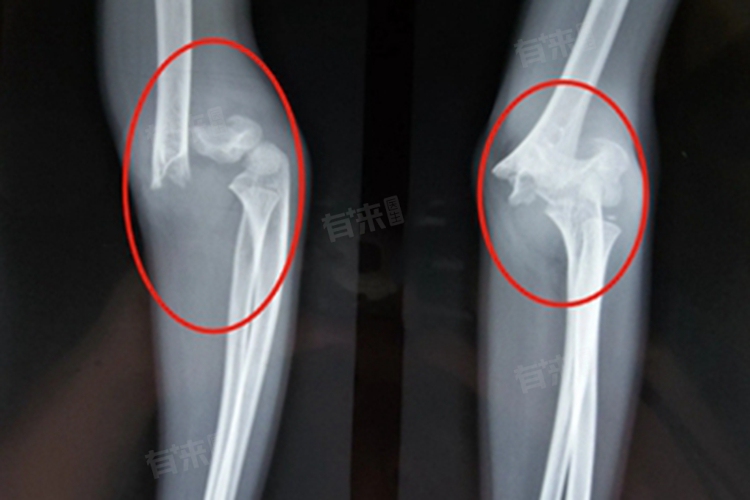

- 但如果骨折已经发生畸形愈合,纠正难度会相对增加,但并非无法纠正。应积极采取手术方式治疗,通过手术切开复位并进行内固定治疗,恢复骨折解剖复位关系。手术时医生会根据患者的具体情况选择合适内固定材料,如钢板、螺钉等,确保骨折部位稳定性。